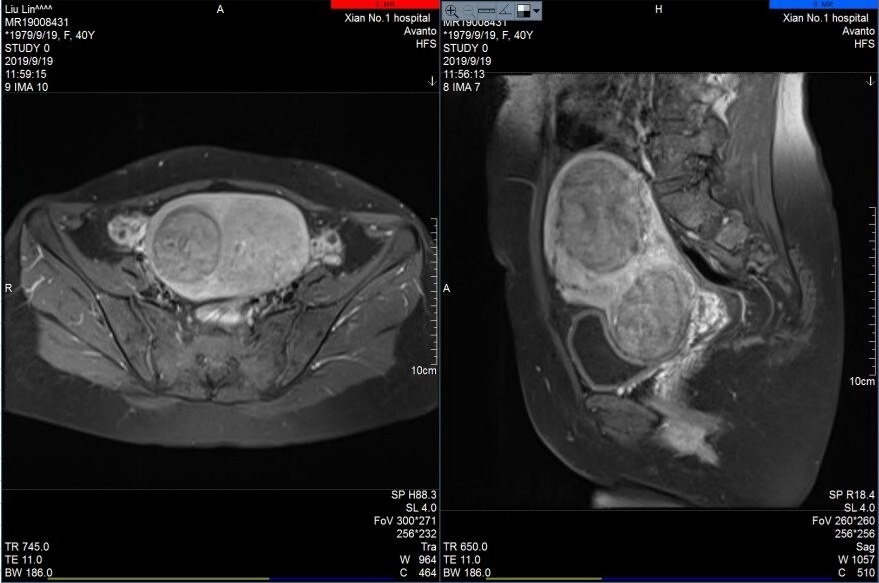

宋迎春主任在海扶刀治疗中心通过对其肌瘤进行上机定位与评估,患者完善了各项入院检查与胃肠道准备后,于2019年9月20日对其肌瘤进行海扶消融治疗,术中只用了752秒的辐照时间,就成功消融了7个肌瘤和1个腺肌瘤病灶,瘤体最大者近7cm,最小肌瘤约1cm,术前术后超声造影显示肌瘤大范围消融坏死,手术达到预期效果,患者十分满意。